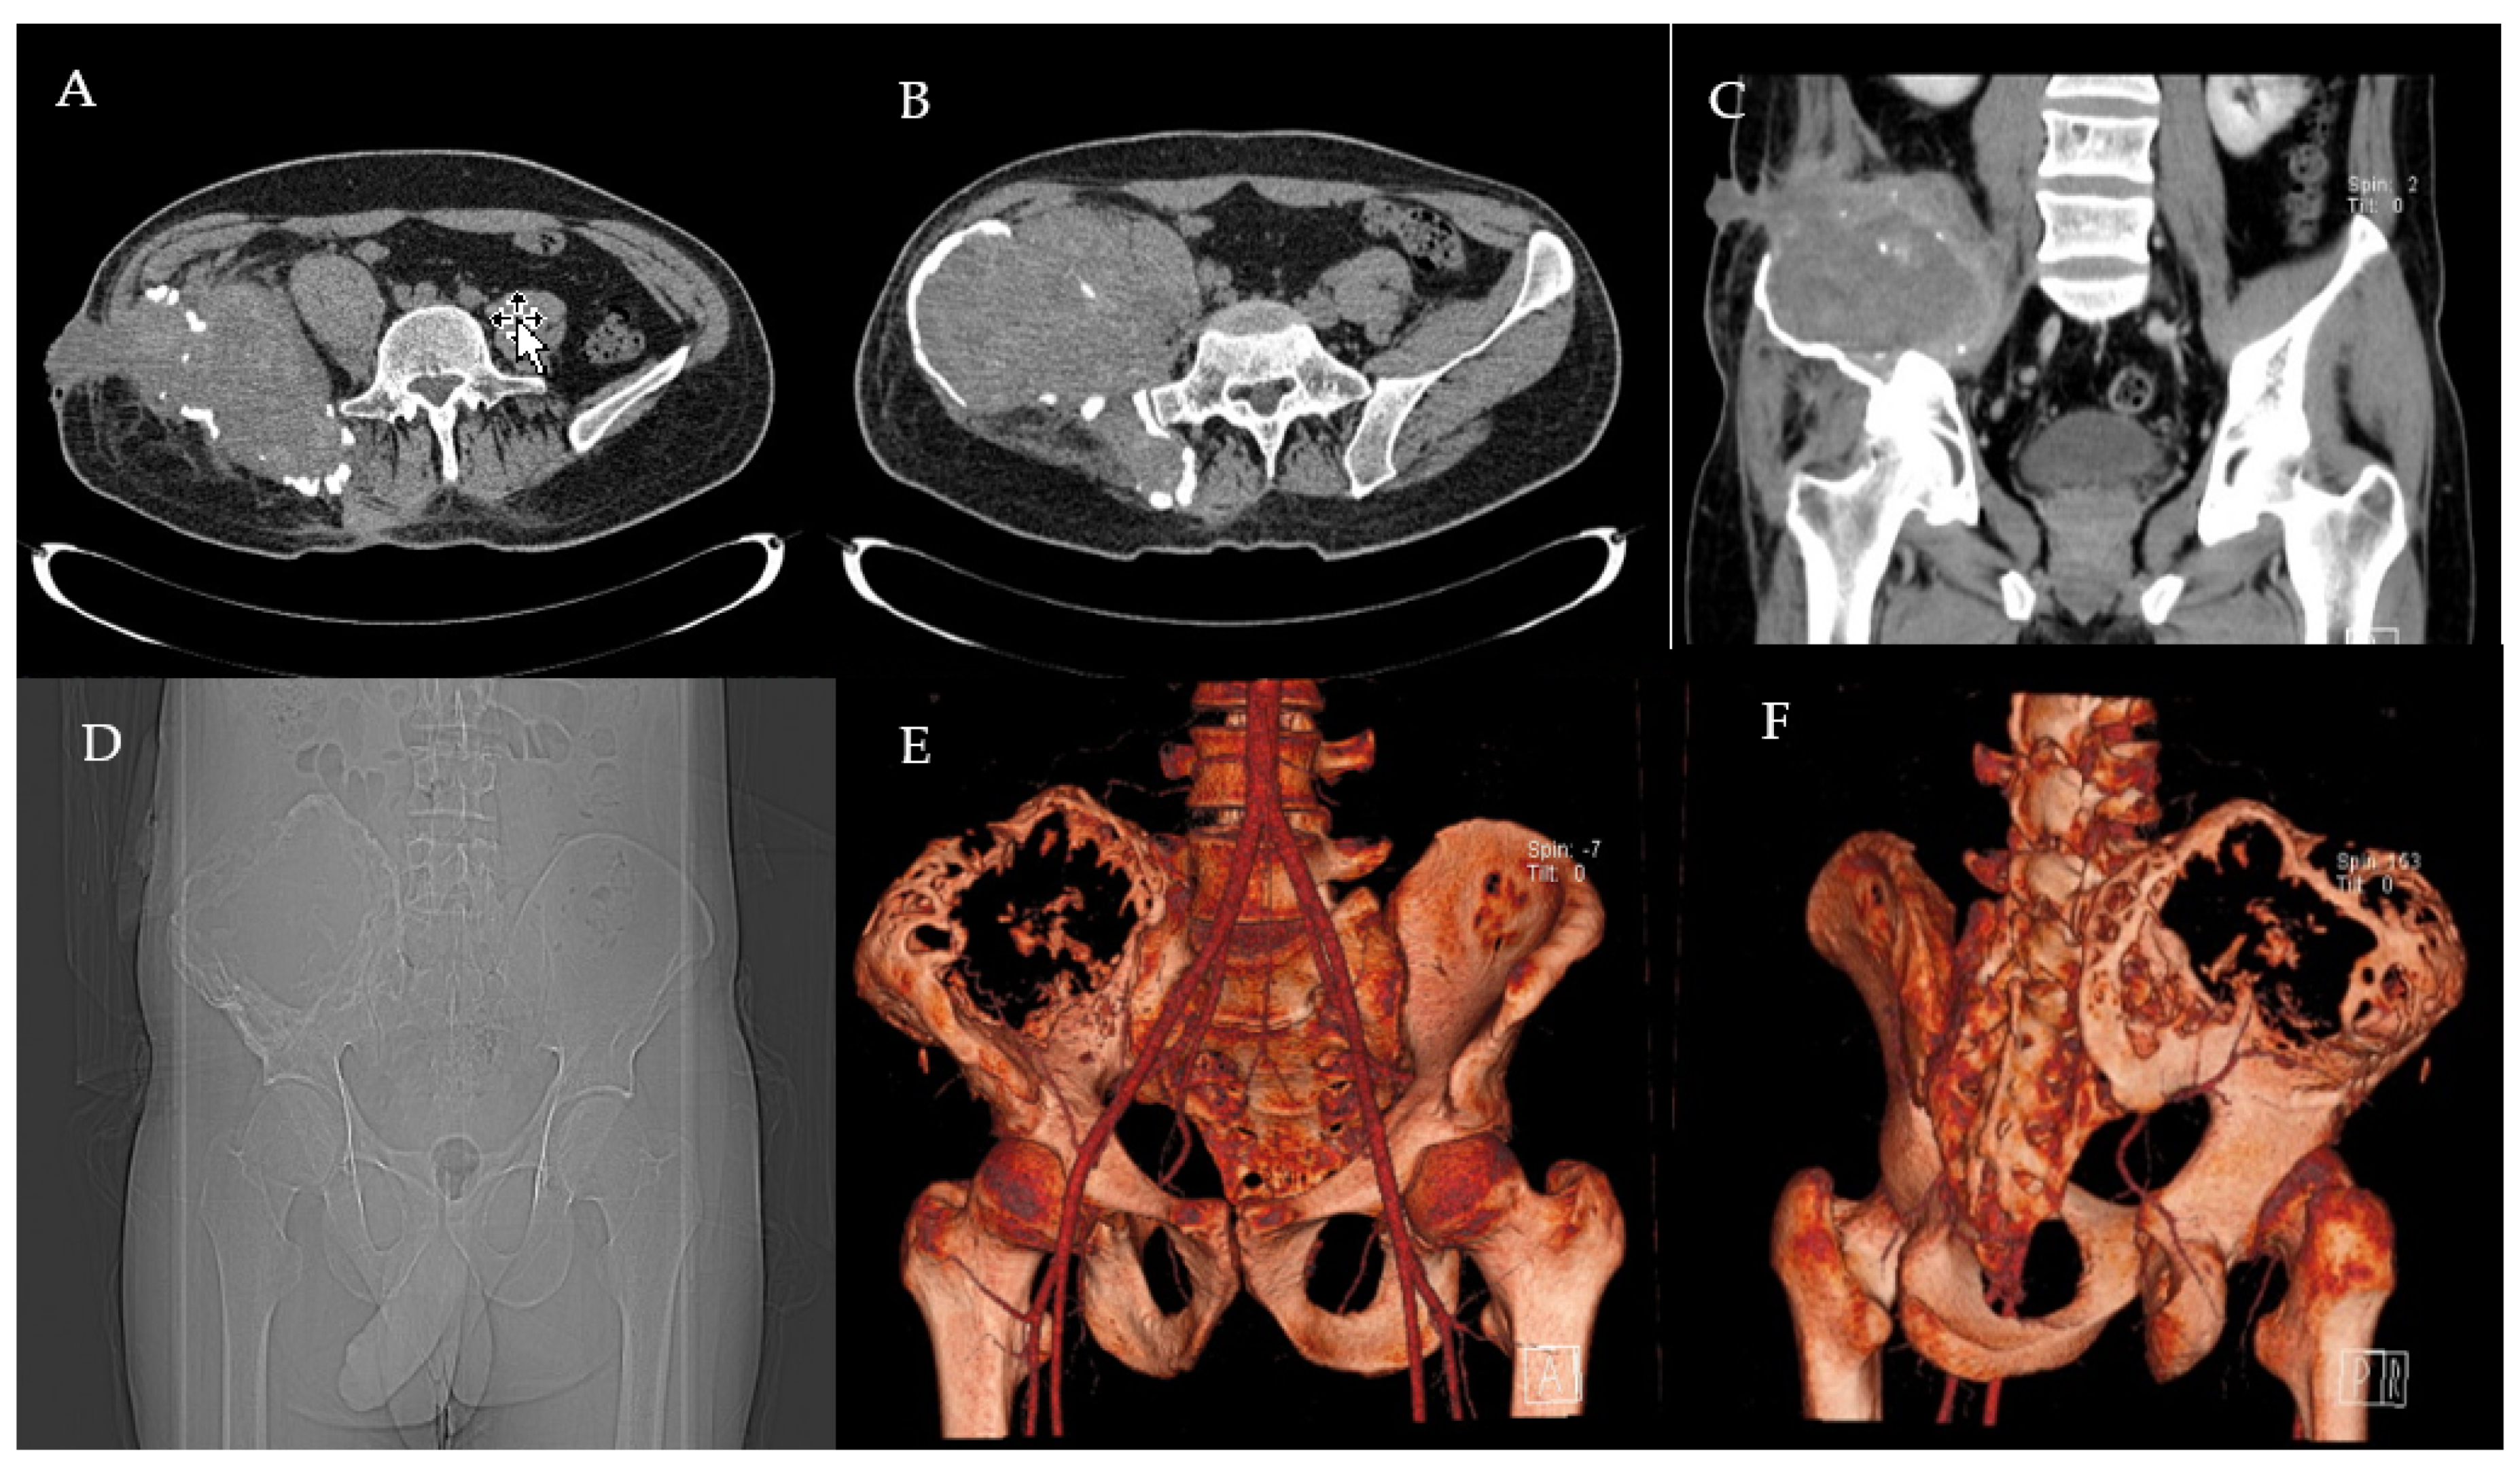

2.1. Clinical History and Instrumental Assessment